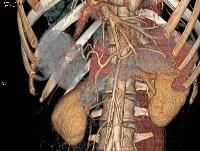

Πρόκειται για γυναίκα ασθενή 32 ετών, η οποία υποβλήθηκε σε αξονική τομογραφία για άτυπα γαστρεντερικά συμπτώματα και άνοδο των ηπατικών ενζύμων. Διαπιστώθηκε συμπαγής μάζα του ήπατος, η οποία εντοπίζονταν τόσο στο δεξιό (τμήματα 5 και 8) όσο και στον αριστερό (τμήμα 4) λοβό. Η ηπατική ογκομέτρηση ανέδειξε ότι τα τμήματα 1, 2 και 3 αποτελούσαν το 30% του συνολικού όγκου του οργάνου (εικόνες 1, 2). Υποβλήθηκε σε δεξιά εκτεταμμένη ηπατεκτομή (εικόνα 3). Στο παρασκεύασμα φαίνεται η μάζα. To μέγεθός της ανέρχεται σε 8 εκατοστά (εικόνα 4). Σε οβελιαία τομή, διακρίνεται η χαρακτηριστική κεντρική ουλή της εστιακής οζώδους υπερπλασίας (εικόνα 5). Ο σχετικός όγκος του υπολοιπόμενου ήπατος ανήλθε στο 64%, ένα μήνα μετά την ηπατεκτομή (εικόνα 6). Η ασθενής είναι ελεύθερη συμπτωμάτων.